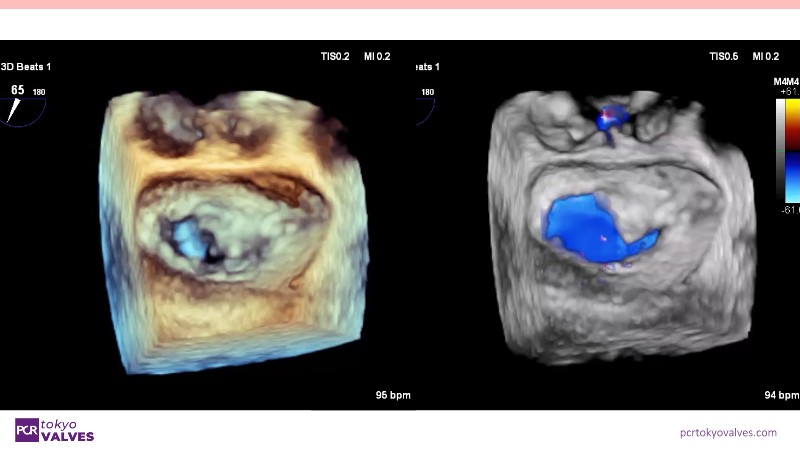

Explore the latest advancements in TEER therapy with this PCR Tokyo Valves 2025 session dedicated to MitraClip. Through expert-led case discussions, gain a deeper understanding of complex scenarios, including restricted posterior leaflet in functional mitral regurgitation, commissure lesion (A3P3), and MitraClip combined with Amulet.

- To understand how the four clip sizes can tailor TEER therapy for optimal outcomes